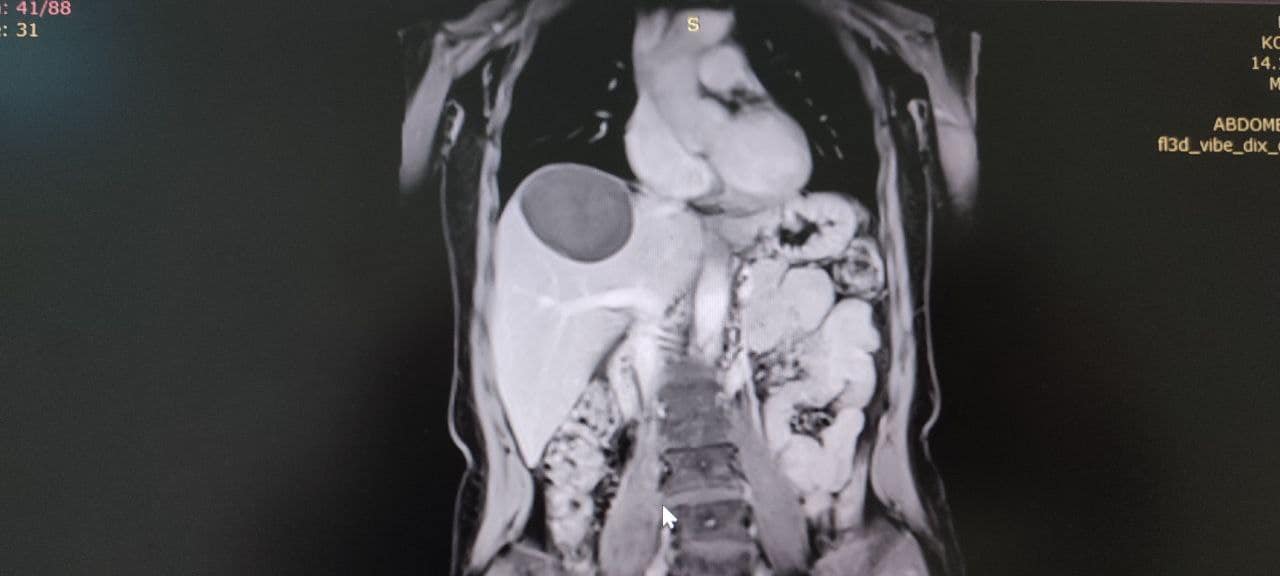

У Володимирське ТМО поступила 50-річна жінка зі скаргами на тиснення і біль у правому підребер’ї. У неї діагностували небезпечне і рідкісне захворювання – ехінококову кісту, яку хірургічно видалили.

Паразитарна кіста в печінці нагадує навколоплідний міхур, всередині якого дозрівають личинки ехінокока. Новоутворення поступово зростає і часом досягає гігантських розмірів (до 50 см у діаметрі).Ехінококозом може захворіти будь-яка людина, імунітету проти цієї хвороби немає. Хвора людина для людей, що її оточують, небезпеки не становить.